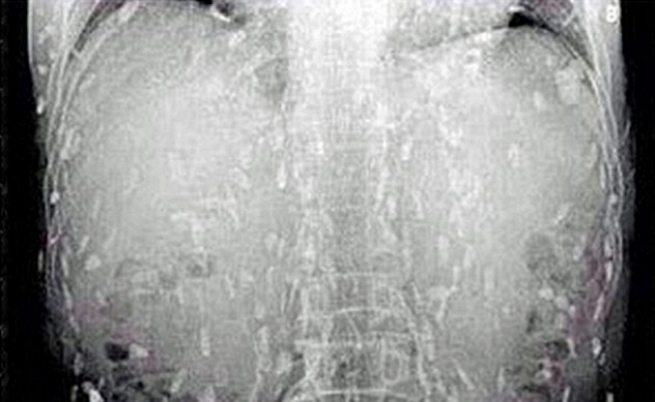

Le radiografie mettono in evidenza le larve diffuse nei muscoli.

Queste radiografie che hanno fatto il giro del mondo, sono di un uomo di 40 anni di Shangai, che si è presentato in ospedale riferendo dolori muscolari da due settimane e sono state attribuite da molte fonti al consumo di sushi.

Alla radiografia, si vedono decine di larve diffuse nel tessuto muscolare: la ragione per cui sono visibili alla radiografia è che il corpo, per proteggersi, crea una barriera di depositi di calcio intorno alle larve. Il fenomeno si chiama cisticercosi e ha una classica presentazione a chicchi di riso in radiografia.

La causa più probabile sono parassiti come Taenia solum o Trichenella spiralis trasmessi dal maiale poco cotto.

Difficilmente il salmone crudo (e quindi il sushi) sono responsabili di questo quadro clinico, perché raramente o mai i parassiti dei pesci (diphyllobothrium latum) si presentano così. La malattia più temibile che si trasmette attraverso il pesce crudo (salmone, tonno, alici marinate ecc) è invece l’Anisakis, che ha un quadro clinico completamente diverso da quello di questo signore di Shangai e che colpisce il tratto gastrointestinale: per proteggersi dall’Anisakis le norme di legge impongono a tutti i ristoranti italiani di servire pesce crudo solo dopo che è stato congelato per almeno novantasei ore a -18 gradi. Assicuratevi che il ristorante dove mangiate le rispetti.

In ogni caso, la condizione presentata nella radiografia si è sviluppata nell’arco di anni, anche se i sintomi di forti dolori muscolari sono emersi solo da due settimane: è comunque un quadro completamente curabile e risolvibile con il trattamento di farmaci specifici per i parassiti, come l’albenzadolo.